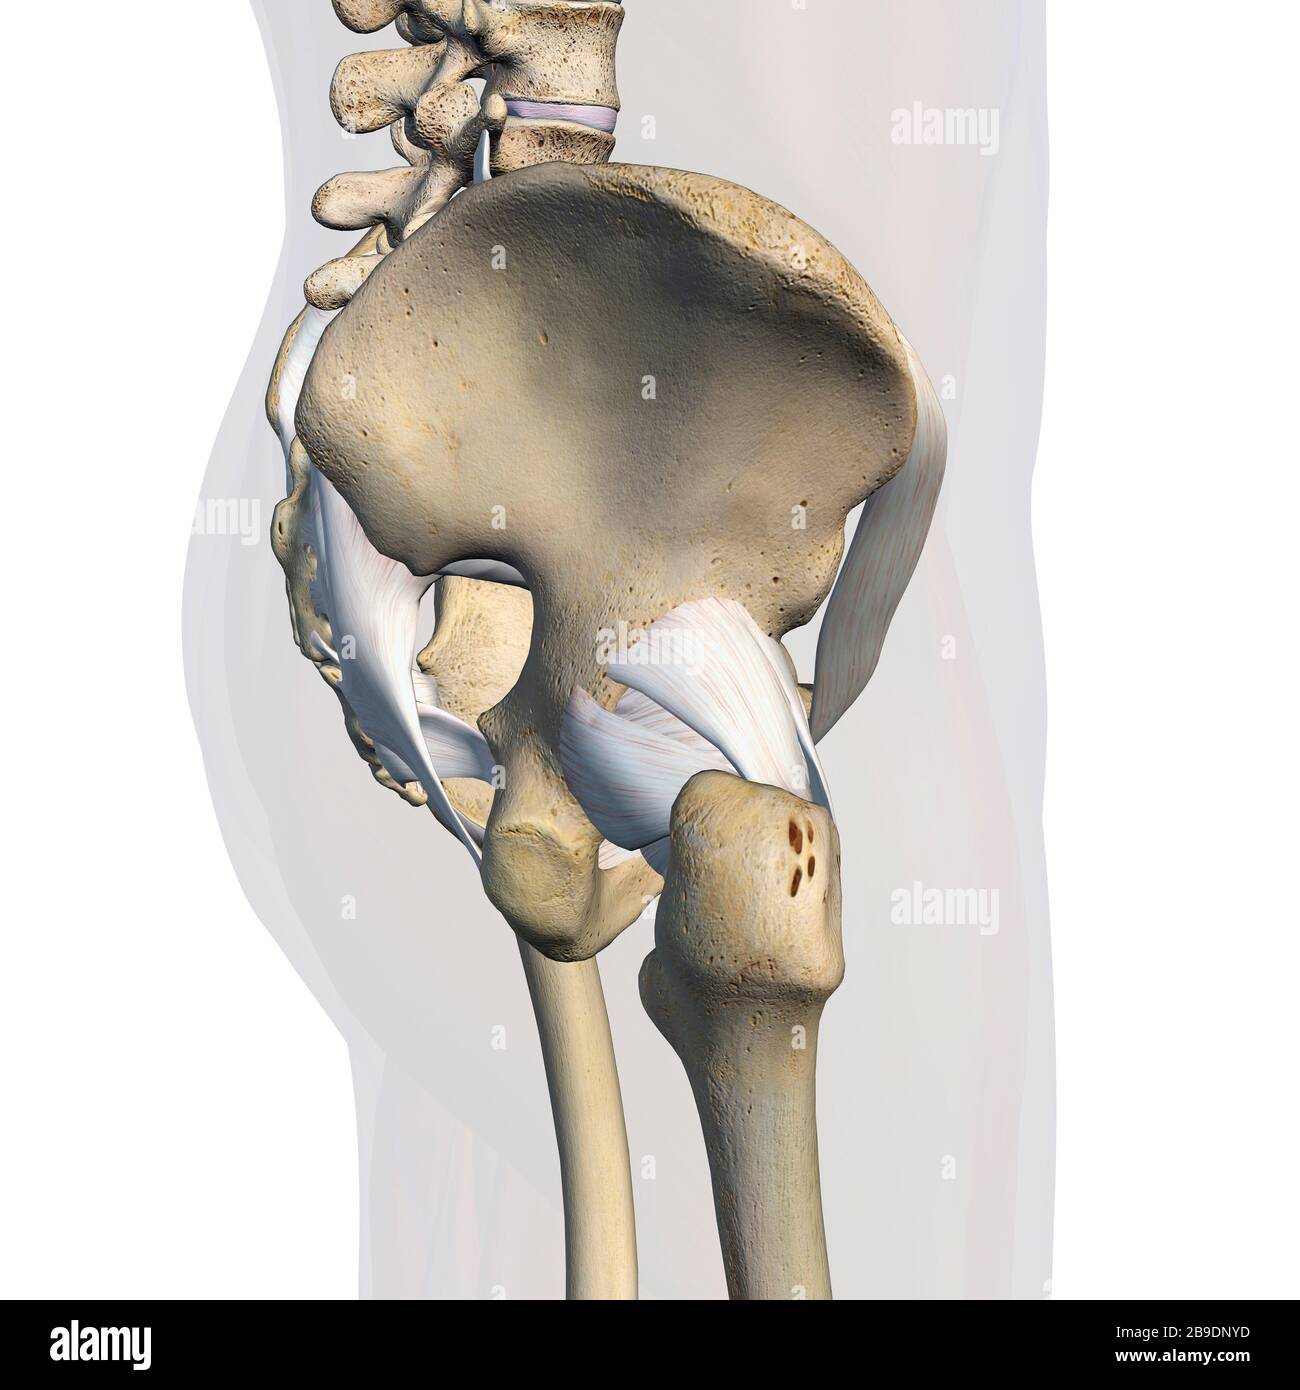

RFWW2CNW–Die männliche Anatomie, Gliedmaßen und hip Muskel- und Skeletterkrankungen Systeme, mit interner Muskelschichten. Vorder- und Rückansicht. schwarzen Hintergrund. 3d-Abbildung.